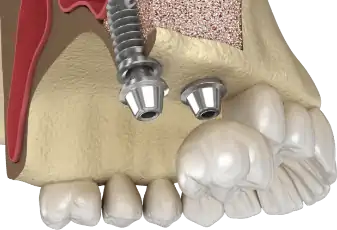

השתלת שיניים

השתלת שיניים - המדריך עם כל המידע הרפואי והמעודכן בזכות מודעות גוברת לחשיבות השמירה על היגיינת הפה, רובנו נהנים משיניים בריאות לאורך זמן. מובן שרפואת שיניים מניעתית אין בכוחה לבטל כל צורך בהתערבות כגון סתימת חורים בשיניים, טיפולי שורש וע